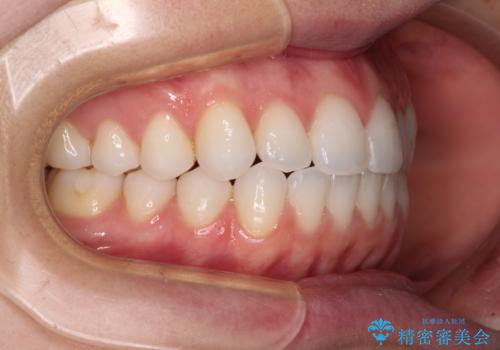

上下前歯が接触しない オープンバイトをインビザラインで改善

- 前歯の上下スペースによる食べにくさを気にして来院された患者様です。

インビザラインにより上下の前歯の隙間を閉じていくこととしました。

上下の奥歯を圧下させるようにすることで、前歯を接触させるように計画しました。

上下の隙間に舌が入り込むことがオープンバイトの原因であったため、舌の筋肉のトレーニングも並行して行い、後戻りの抑制を図りました。